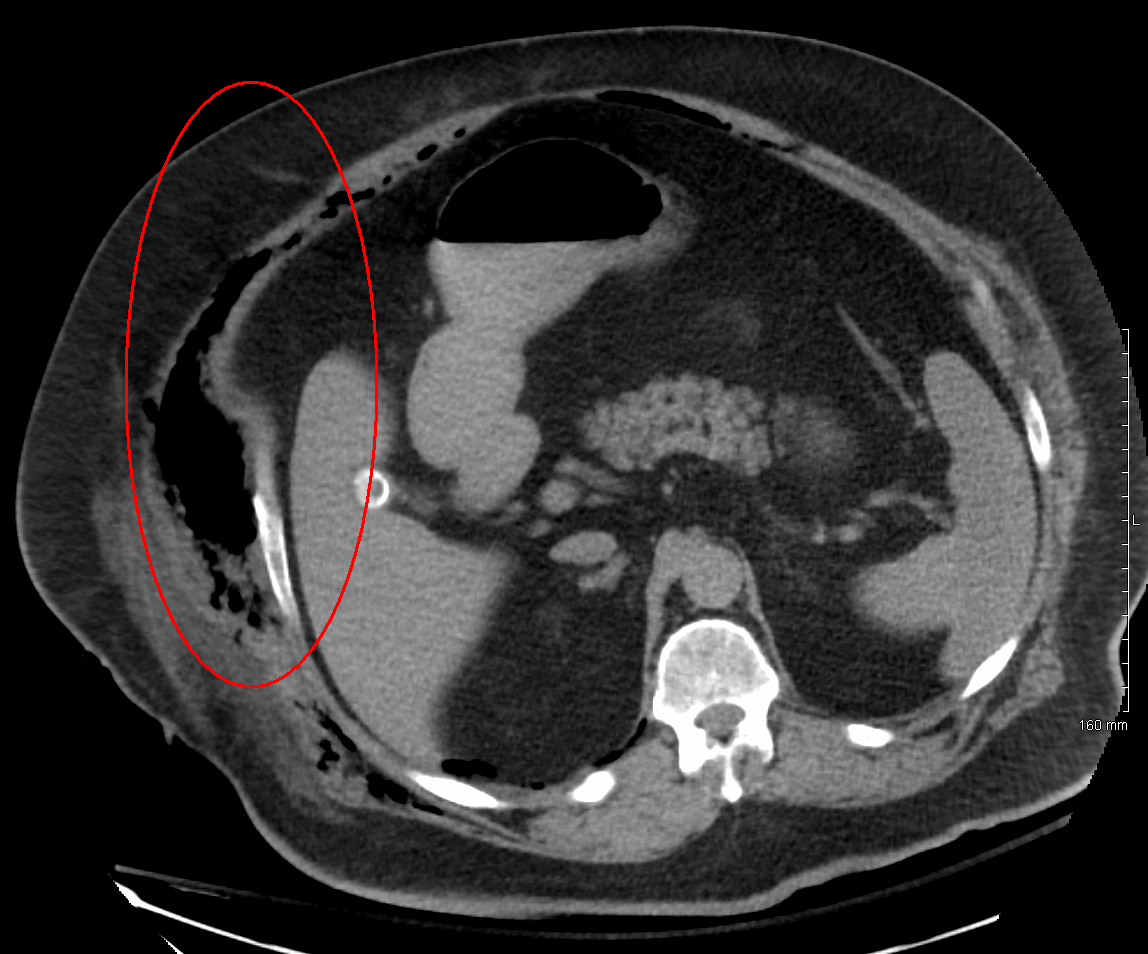

괴사성 근막염은 증상으로 진단하는 것이 가장 좋지만, 빠른 수술이 필요하기 때문에 영상 촬영을 하는 시간 지연이 문제가 될 수 있다.[15] 따라서 괴사성 감염의 징후가 확실하다면 영상 촬영은 필요하지 않을 수 있다. 그러나 초기 증상이 뚜렷하지 않아 영상 촬영이 진단에 도움이 되는 경우가 많다.[15]컴퓨터 단층 촬영술(CT)은 속도와 해상도 면에서 괴사성 근막염을 진단하는 데 가장 편리한 도구로, 약 80%의 괴사성 근막염 사례를 감지한다.[16] CT 스캔은 근막 비후, 부종, 농양 형성을 보여줄 수 있다.[6][15] 조직 내 가스를 자기 공명 영상(MRI)보다 더 잘 감지할 수 있지만, 영상 검사에서 가스가 없는 괴사성 근막염이 나타나는 경우도 드물지 않다.[15] CT는 괴사성 근막염으로 인한 합병증을 평가하고 감염의 원인을 찾는 데도 도움이 된다.[15] 임산부나 신장 문제가 있는 환자에게는 사용이 제한될 수 있다.[15]